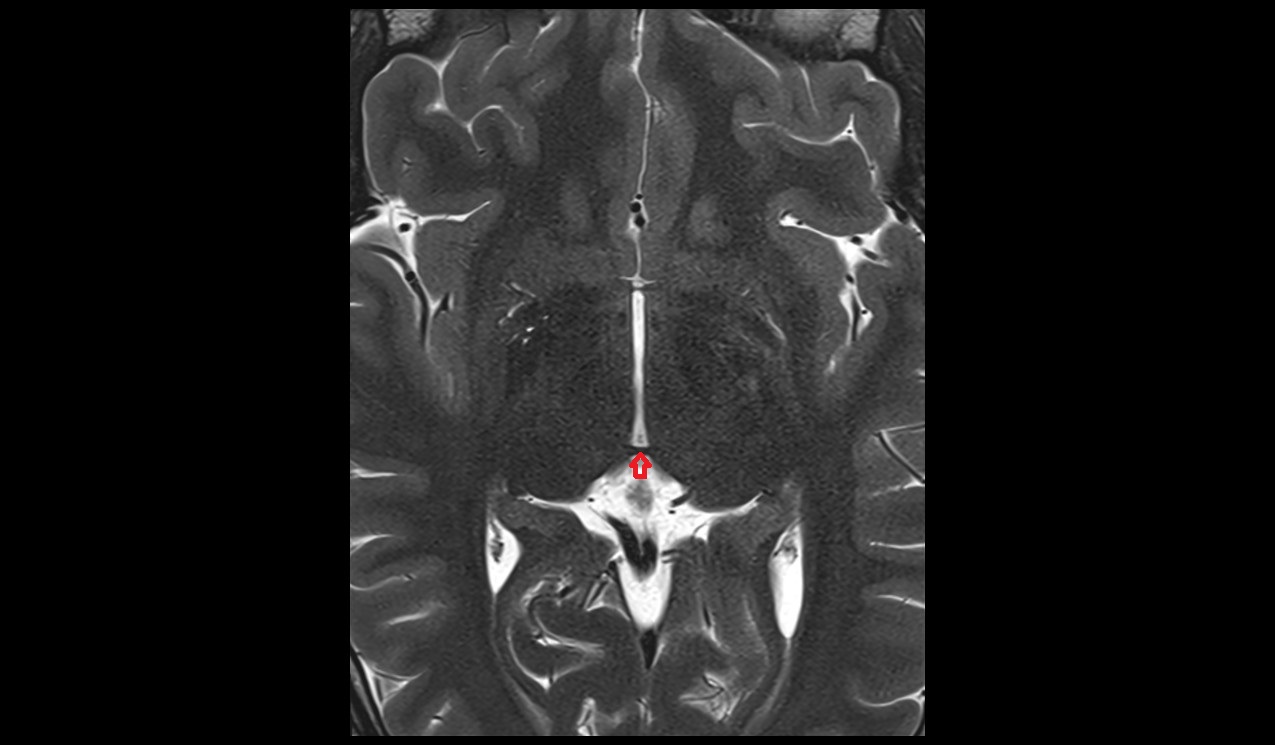

- Conus medullaris